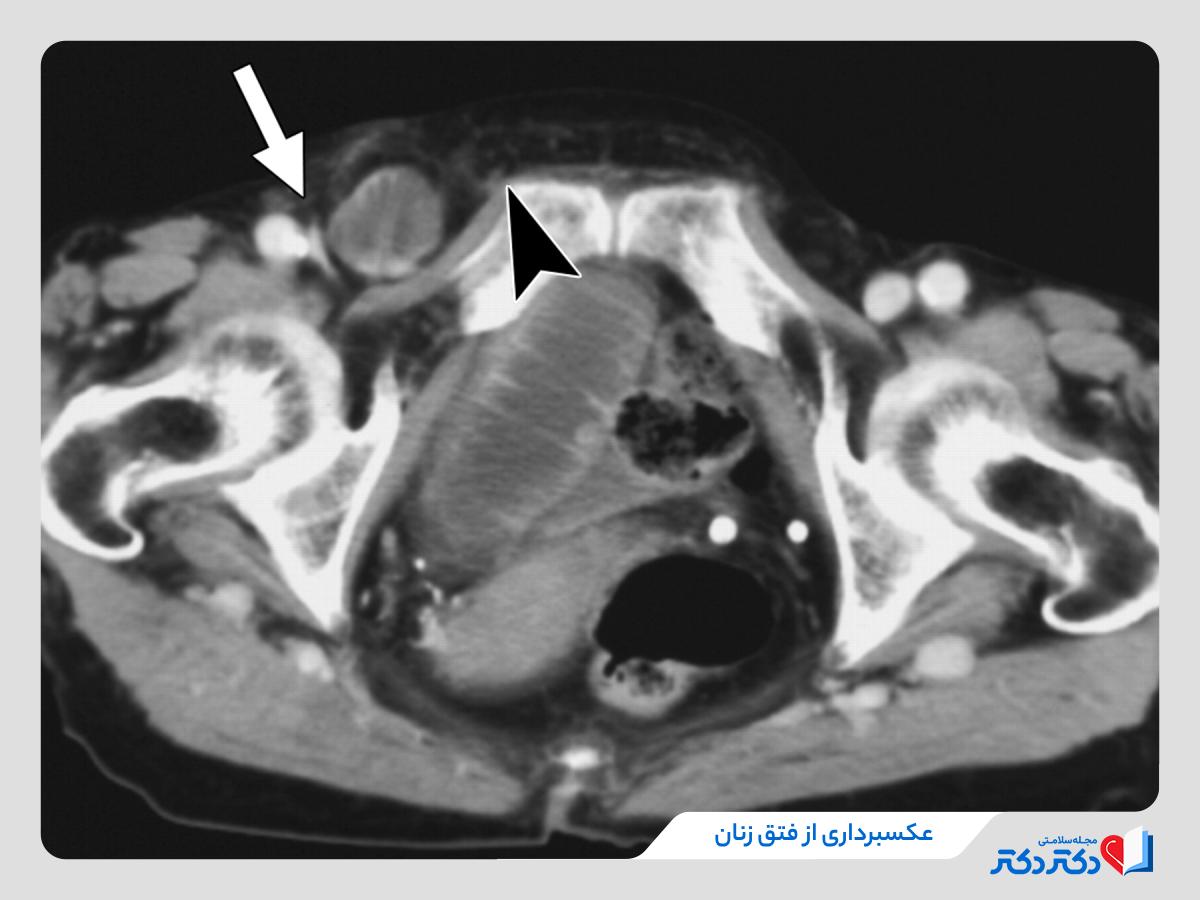

- MRI یا CT اسکن؛ در مواردی که معاینه و سونوگرافی کافی نباشد یا نیاز به برسی دقیقتر وجود داشته باشد.